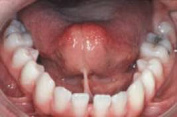

Bändchen (hier ein zu kurzes

Zungenbändchen), die zu nah an den Zähnen

ansetzen, können an Zahninnenseiten einen

Zahnfleischrückgang provozieren.